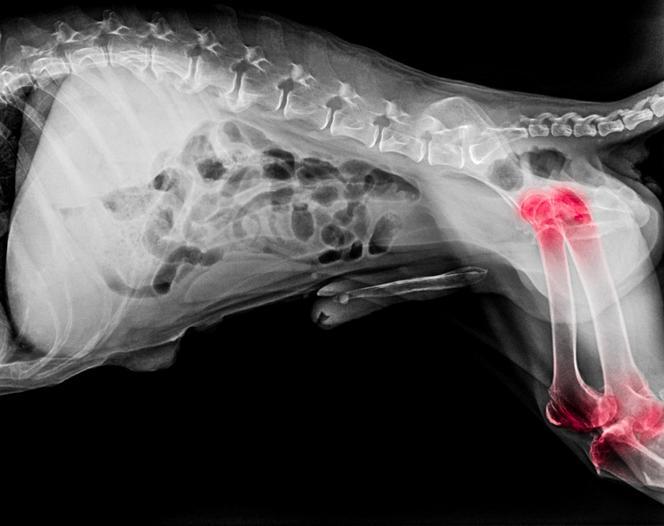

A artrose em cães é uma doença degenerativa e progressiva das articulações, sendo mais comum em cães mais velhos. A cartilagem, que reveste e protege as articulações, é destruída em cães com artrose. Além disso, ocorre um crescimento ósseo anormal ao redor dela, o que resulta numa superfície irregular, inclusive com fragmentos desprendidos. Esses danos podem ser observados nas radiografias. Uma articulação nesse estado permite o atrito das superfícies, o que piora o processo de degeneração e causa uma dor considerável que, logicamente, afetará a mobilidade do cachorro.

É possível distinguir uma artrose primária, consequência do envelhecimento, e outra secundária, que é a que aparece após um fator desencadeante como um traumatismo ou uma malformação como displasia. A obesidade também pode danificar as articulações e existem doenças sistêmicas que podem causar claudicação ou degeneração nas articulações. A artrose primária costuma afetar mais de uma articulação, enquanto a secundária é mais pontual. Por meio de radiografias, o veterinário poderá confirmar o diagnóstico.